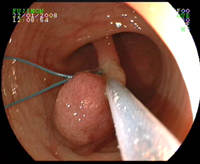

Biopsie exerese à la pince d'un polype

Injection sous muqueuse sous le polype